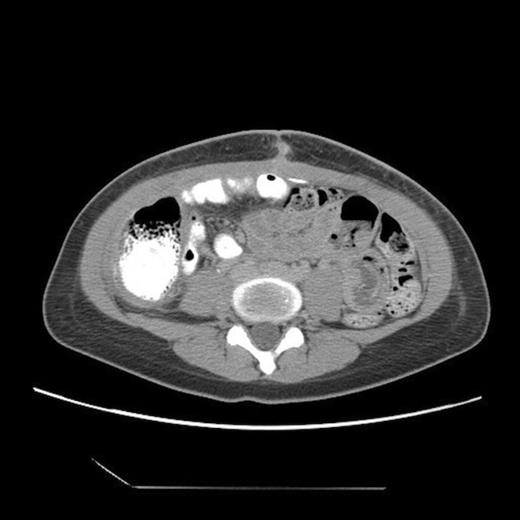

Abdominal CT, axial view, demonstrating a large fluid compartment surrounding the VP shunt catheter resulting in mass-effect, hydronephrosis, and displacement of the intra-abdominal contents

She eventually sought medical attention when she began developing diffuse, unremitting bilateral lower quadrant pain as her abdomen continued to enlarge (Fig. 1). A urine pregnancy test on admission was negative. Abdominal CT demonstrated a large fluid compartment surrounding the VP shunt catheter resulting in mass-effect, hydronephrosis, and displacement of the intra-abdominal contents (Fig. 2 and 3), establishing a diagnosis of APC.

The patient underwent laparoscopic cyst drainage with removal of the cyst wall. A total of 12.7L of fluid was drained. Culture results and routine labs were all negative. A post-operative CT demonstrated complete resolution of the fluid compartment (Fig. 4). The VP shunt catheter was initially left in the abdominal cavity. One month later, however, she developed significant recurrence of fluid collection (Fig. 5) and lethargy from malfunction of the VP shunt. The recurrent fluid was drained under ultrasound guidance, and her abdominal shunt catheter was removed. A new shunt catheter was placed in the right atrium, and the patient made a full recovery without any further complications.